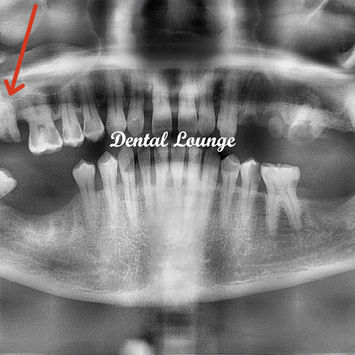

Surgical Removal of Retained Roots of Tooth #17

Tooth #17 showed mesio-occlusal caries extending to the pulp.

Slight metallic sound on percussion, raising suspicion of ankylosis.

Initial attempt at extraction under LA led to coronal fracture and retained roots.

Radiographic findings: fused 3-rooted retained roots, dense surrounding bone.